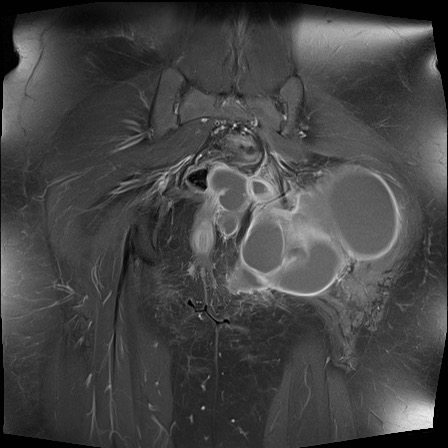

Hình ảnh X-quang khung chậu của bệnh nhân viêm khớp do lao tại khớp háng trái.

Có hẹp khe khớp kín đáo kèm theo xơ cứng dưới sụn tại khớp háng trái.

Các dấu hiệu X-quang này không đặc hiệu và rất có thể là biểu hiện của thoái hóa khớp.

Tiếp tục xem hình ảnh MRI…

Điều bất ngờ với tất cả mọi người là có nhiều ổ áp-xe.

Khi hình thành áp-xe lan rộng như vậy trong khi biểu hiện lâm sàng lại tối thiểu, cần luôn nghĩ đến viêm khớp do lao.

Chẩn đoán viêm khớp do lao được xác lập bằng chọc hút dịch khớp.